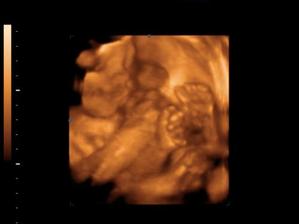

Tak uz som aj ja na svete,narodil som sa 3.11.2007 o 21:04 troska som maminu potrapil,bo som isiel sekciou.Volam sa Tobias,ked som sa narodil som vazil 4.280g a meral 53cm.